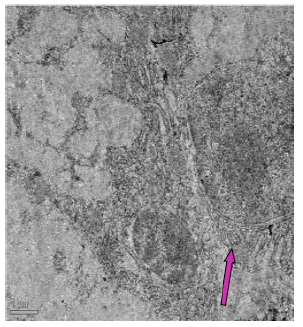

In the fluoride-treated rat, the endoplasmic reticulum had dilated cisternae, contained the virus particles, characterized by an electron-dense core enveloped by one or two membranes (Figure 58). Under the microvilli, a noticeable terminal web was seen and prominent lateral interdigitations were visible between the cells, suggesting complex folding or invaginations of cell membranes. Additionally, the mitochondria appeared swollen with few disintegrated cisternae (Figure 59). The jejunum of fluorotic rats displayed vacuolations. The presence of lysosomes and vesiculated RER was observed in the cytoplasm (Figure 60).

Figure 59: Transmission electron micrograph of jejunum of rat treated with 600 mg fluoride showing interdigitations (↑) swollen mitochondria with few disintegrated cristae. Dilated reR (↑) was also seen. X 2550.

In the ileum of control rat, distinct defensin-rich granules were visible within the Paneth cells, indicating their role in innate immune defence. Furthermore, mitochondria and different secretory granules were also present (Figure 61) and had rough endoplasmic reticulum throughout the cytoplasm (Figure 62). In fluoridated rats, the Golgi apparatus of the ileal tissue appeared aberrant and hypertrophied. The mitochondria had lost their characteristic appearance and were obscured suggesting that high fluoride exposure disrupts cellular structures and functions within the ileum (Figure 63). Significant vacuolations, suggestive of the presence of spaces within the tissue, disintegrated mitochondria and irregularly shaped nuclei were visible (Figure 64). The ileum exhibited irregularities in the rough endoplasmic reticulum (rER) and disruptions in other cytoskeletal components (Figure 65).